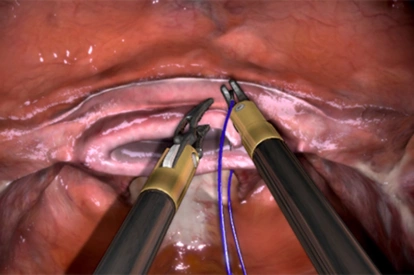

- Highly realistic graphics of human anatomy and simulation of tissue response to instruments

- Tutorials: videos of experts performing tasks and procedures on the simulator along with videos of real procedures